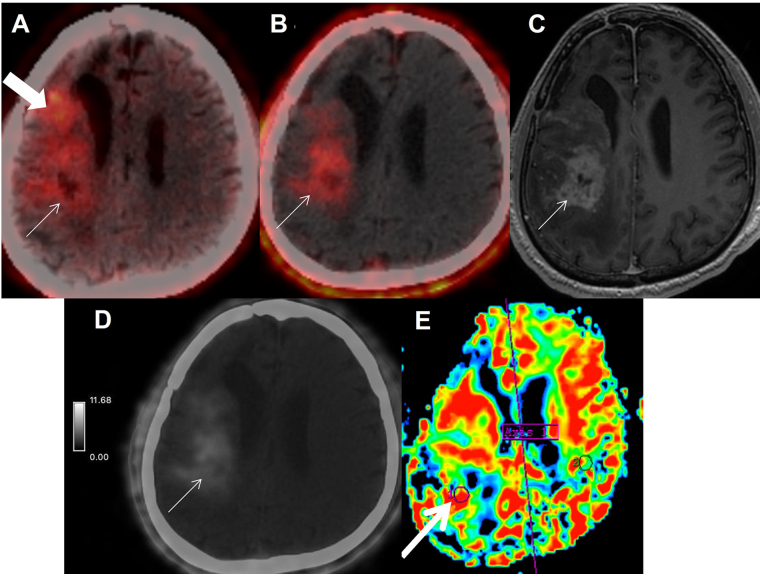

Fibroblast-activated protein (FAP) expression in glial cells is attributed to FAP-positive foci on tumor vessels and neoplastic cells. Preclinical and pilot studies have shown FAP expression in high-grade gliomas. We aimed at comparing PET imaging with FAP-inhibitor (FAPI-PET) with current standard, i.e., fluoro-ethyl tyrosine (FET) PET in post-treatment setting to differentiate recurrence and post-treatment changes. 6 patients with WHO Grade III and IV glioma who received standard treatment underwent Ga-68-FAPI-04 PET/CT (FAPI-PET/CT). Tracer uptake greater than background was considered positive. FET PET was performed and interpreted as per institutional standards, which formed the basis of treatment decision. There was concordance between FAPI expression and FET uptake in 5 patients suggestive of disease recurrence. There was no FAPI expression seen in 1 patient, in whom FET PET was suggestive of post-treatment changes. FAPI PET uptake correlated with amino acid expression to differentiate post treatment changes from recurrence in high-grade glial tumors; further validation with prospective study and histopathological confirmation is needed.

Abstract Image